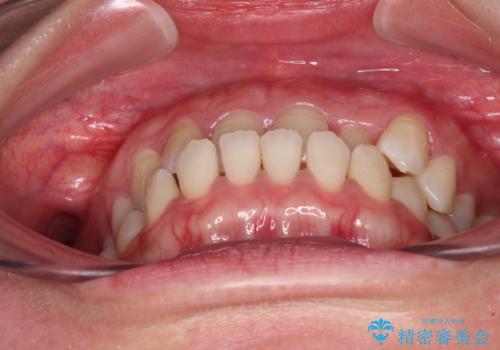

- 全顎的なクロスバイトと反対咬合を気にして来院された患者様です。

骨格的に下顎が前方位にありましたが、歯並びにより下顎が本来の位置よりも前方位に誘導される咬み合わせとなっていました。

上顎歯列および上顎骨が下顎に対して狭小であることが原因であるため、上顎の急速拡大装置を使用して上顎骨を側方に拡大することで反対咬合を改善し、ワイヤー装置で歯列を整えることとしました。